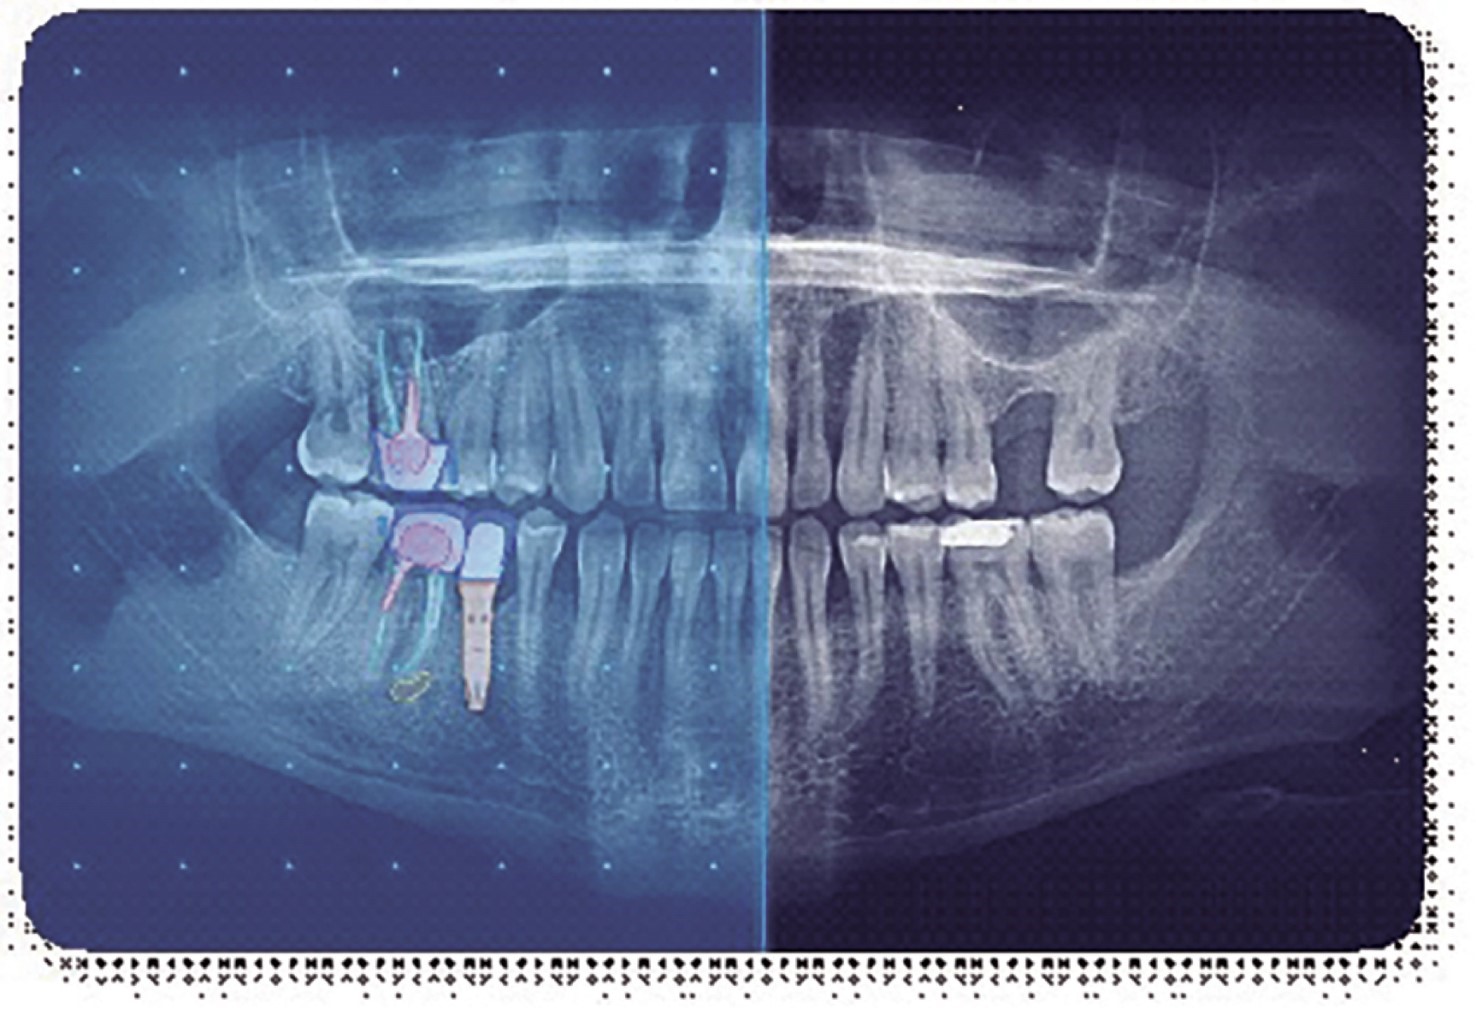

Artificial intelligence, uses of software and its applications in dental radiology.

Introduction: artificial intelligence (AI) is used in different fields, such as medicine, with multiple results, so the use developed in dental radiology can add importance to the dental profession. Objective: the purpose of this work was to identify the various artificial intelligence software applications in dental radiology. Material and methods: an electronic review of the information related to AI software applied in dental radiology was carried out. The inclusion criteria consisted of AI-based technology in dental x-rays and their applications in dental practice. Results: within the AI software, we could find the following: AI Dental Image from Carestream, Pearl by DentalMonitoring, Vizi AI from Vatech, and Diagnocat: Promadent AI Insights. And some companies that use AI in dental radiology, such as Zebra Medical Vision, Allisone Technologies, and DentiMax, With the following applications in dental radiology, they improve diagnostic accuracy, workflow efficiency, detect dental problems at an early stage, diagnose cavities, gum diseases, dental fractures, and maxillofacial tumors, and also support density measurement of bones and the location of cephalometric reference points. Conclusions: in the last decade, multiple AI software programs have been developed that have the potential to revolutionize dental radiology. By improving diagnostic accuracy and early detection of dental problems, AI can help dentists provide more accurate and safer dental care to their patients.

Figure 1